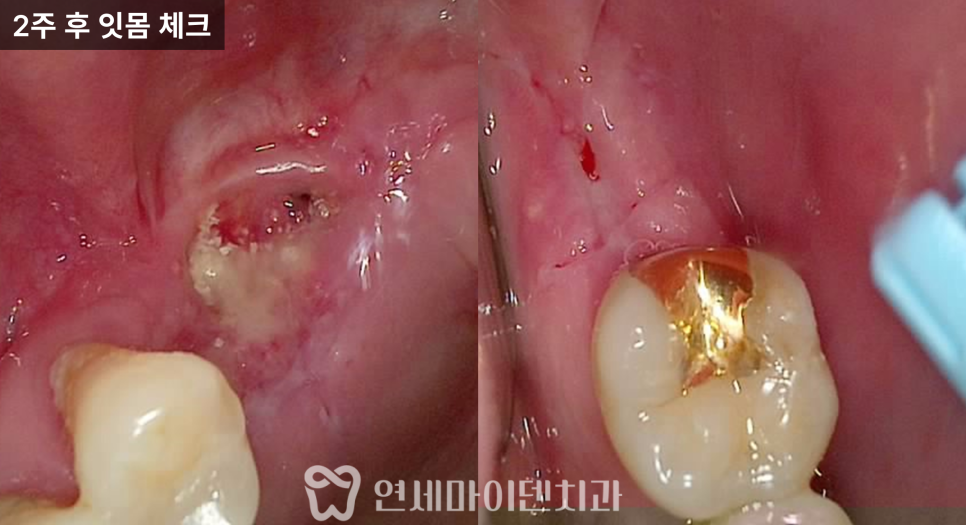

치료 후 잇몸 회복 과정

임플란트 식립 시

초기 고정력이 충분히 확보되어

힐링 어버트먼트를 연결해

1차와 2차 수술을 동시에 마무리할 수 있었습니다.

실밥 제거 시점에는

기존에 있던 고름 주머니가 사라졌고,

잇몸은 비교적 빠르게

안정된 상태로 회복되는 모습을 보였습니다.

이후 한 달 경과에서도

염증 재발 없이 깨끗한 상태가 유지되었습니다.

염증 제거 후 잇몸 변화

치료 후 약 2주가 지나면서

이전에 붓고 출혈이 있던 잇몸은

눈에 띄게 안정되었습니다.

잇몸 조직은

염증의 원인이 제거되면

빠르게 회복

되는 특성이 있습니다.

다만 이 상태를 유지하려면

이후 관리가 매우 중요합니다.